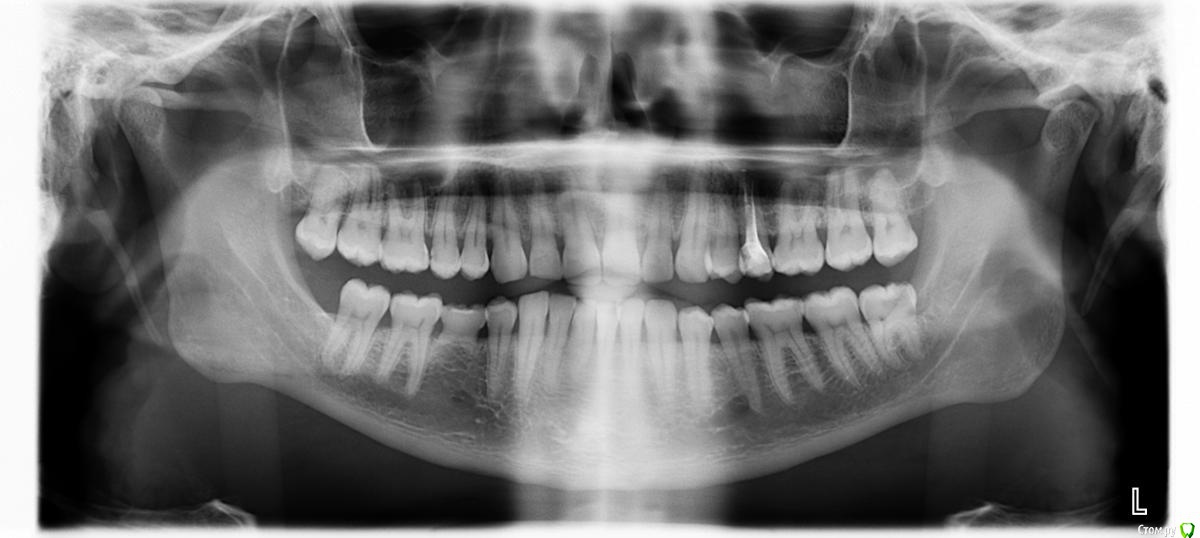

Romko Опубликовано 5 мая, 2016 Поделиться Опубликовано 5 мая, 2016 Недавно откололась часть зуба, пришлось идти в стоматологию. Зуб залечили. Заодно решил сделать снимок, основная цель была посмотреть - что там с молочным зубом и ждать ли коренной. Врач сказала - зародыша коренного нет и его ждать бесполезно(да?). И корни почти растворились, скоро ему "ой всё". Собственно, волнуют вопросы: Коренного действительно не ждать? Сколько, примерно, может еще "прожить" молочный? И куда мог деться зародыш коренного и зуб мудрости с той же стороны. Я его не удалял(вообще не удалял ни одного коренного зуба еще). Но нет ни самого зуба мудрости, ни зародыша. Ссылка на комментарий

red_butler Опубликовано 5 мая, 2016 Поделиться Опубликовано 5 мая, 2016 Коренного действительно не ждать? нет Сколько, примерно, может еще "прожить" молочный? уже не долго И куда мог деться зародыш коренного и зуб мудрости с той же стороны. Я его не удалял(вообще не удалял ни одного коренного зуба еще). Но нет ни самого зуба мудрости, ни зародыша. произошел сбой, так бываетНужна консультация ортодонта и ортопеда. Молочный зуб поменяете на имплант. 1 Ссылка на комментарий

Zlata-doctor Опубликовано 5 мая, 2016 Поделиться Опубликовано 5 мая, 2016 зачатка нет и не будет уже, к сожалению. Молочный зуб не удаляйте, может простоять еще долго, хотя по снимку корни практически рассосались. Как станет подвижным или сам удалится-поставите имплант 1 Ссылка на комментарий

Brigita Опубликовано 5 мая, 2016 Поделиться Опубликовано 5 мая, 2016 Молочный и правда может долго простоять с такими корнями. 1 Ссылка на комментарий

red_butler Опубликовано 5 мая, 2016 Поделиться Опубликовано 5 мая, 2016 Молочный и правда может долго простоять с такими корнями.а может и завтра выпасть 1 Ссылка на комментарий